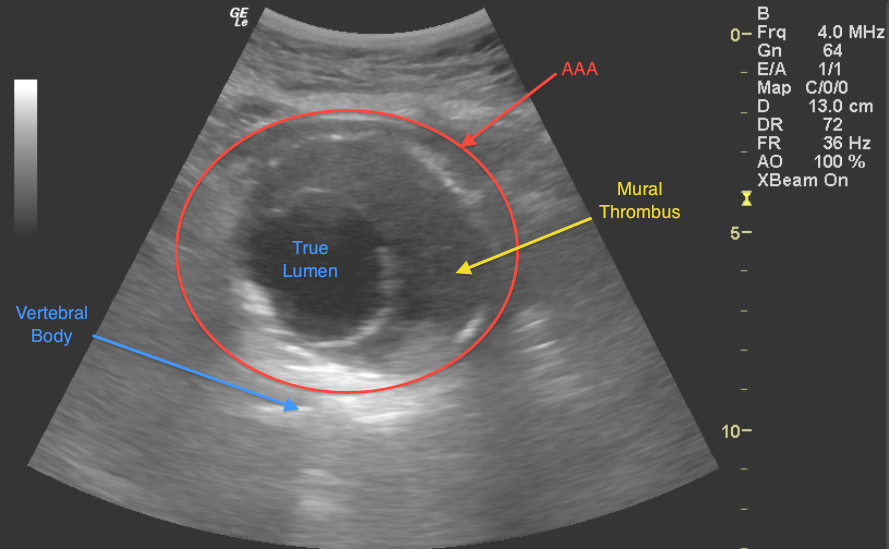

- Identify normal chest and abdominal anatomy

- Patient anatomy

- Knowledge of common pitfalls

- Appreciating technical limitations